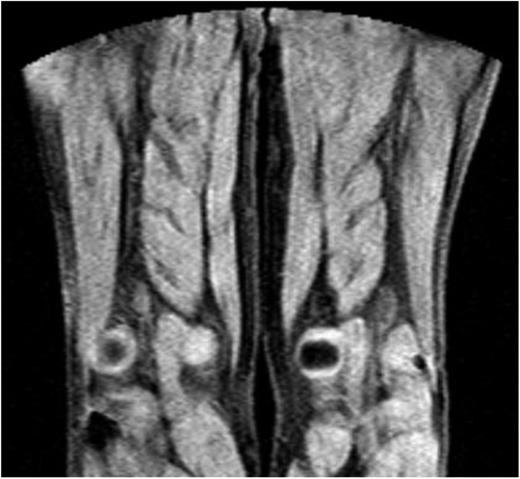

MRDTI was normal in all 42 patients of group 2, who had chronic thrombosis on CUS and no symptoms of acute recurrent DVT. Figure 2 depicts the normal MRDTI signal in a patient from study group 2 with asymptomatic residual thrombosis.

MDRTI image of a patient with ultrasonography-proven residual DVT but no acute recurrent thrombosis in the popliteal vein of the right leg. The scan did not indicate an abnormal MRDTI signal.

The sensitivity of MRDTI was 95% (95% CI, 83% to 99%), and specificity was 100% (95% CI, 92% to 100%; Table 2). By using a selected group of study participants with an overall 48% frequency of acute recurrent DVT, the negative predictive value of MRDTI was 95% (95% CI, 83% to 98%), and the positive predictive value was 100% (95% CI, 88% to 100%).

Our study did not establish the definite role of MRDTI in the most optimal diagnostic algorithm for suspected acute recurrent ipsilateral DVT. The group 1 patients do not represent the full spectrum of patients with an acute recurrent DVT; those being given anticoagulant treatment with longer symptom duration or those with inconclusive CUS results were not included. Second, the strength of a D-dimer test in combination with a clinical decision score to identify patients with a very low pretest risk in this specific patient category who can be managed without imaging is yet to be established. Although in 1 study, normal D-dimer levels were shown to rule out the presence of acute symptomatic recurrent DVT, the broad confidence interval and high point estimate of 6.0% (95% CI, 2.6% to 11%) for recurrent disease despite a normal D-dimer level in that study argue against a role for D-dimer as a stand-alone test to rule out recurrent DVT.14 MRDTI has the potential to be used as a first-line imaging test, or as a second-line test for those patients in whom ultrasonography does not provide a conclusive test result. In addition to the high diagnostic accuracy, the fast, noninvasive, patient-friendly nature of MRDTI is a strong argument for the former scenario. Conversely, acute accessibility in the emergency department setting may be limited in some hospitals. Importantly, in the latter scenario of MRDTI being the second test after inconclusive CUS, standardized reference ultrasonography recordings should still be performed in all patients after treatment cessation. Strengths of the study include the application of an efficient design. One group of patients with symptomatic ipsilateral recurrent DVT, based on strict CUS criteria as well as a positive D-dimer test, formed the basis for an accurate sensitivity estimation, whereas patients with a residual thrombosis and negative D-dimer test provided a precise specificity estimation. By this design, this is the first study that was able to address the accuracy of MRDTI in a specific series of patients with acute ipsilateral recurrent DVT. This design had also been successfully applied previously for the evaluation of a new scintigraphy in the diagnostic work-up of suspected recurrent ipsilateral DVT.16 Furthermore, exclusion criteria were designed to exclude only those patients who could not undergo MRDTI and those in whom the group 1 or 2 status could not be established with 100% certainty. In addition to evaluating the diagnostic accuracy of MRDTI, we studied its feasibility in daily clinical practice. Not only did we demonstrate a high reproducibility of the MRDTI results, MRDTI images in all participating hospitals were of good quality, suggesting that MRDTI could be broadly applicable on different MRI machines. The most important limitation of the study is that, by design, the subgroup of patients for which it is hoped MRDTI would be most helpful (ie, those with suspected recurrent DVT and inconclusive CUS) was not part of this study. A further limitation was that only patients with normal D-dimer levels were selected in the control group without recurrent DVT. Although this indeed is a strong argument for the absence of acute DVT, higher D-dimer levels are common in asymptomatic patients after completion of a 6-month treatment period for acute venous thromboembolism (VTE) and are associated with more extensive residual thrombosis as well as a higher recurrence risk.17,18 Hence, although it is unlikely, we cannot rule out the possibility that the excellent specificity observed in our study might be an overestimation resulting from the selection of relatively nonsevere cases of residual thrombosis. Finally, the MRDTI images were read by readers who were already experienced MRDTI readers, possibly resulting in an overestimation of the reproducibility of the readings and generalizability to other settings. Even so, the images are relatively easy to read (Figures 1 and 2), and specific training of radiologists, in our experience, does not prove to be a major effort.